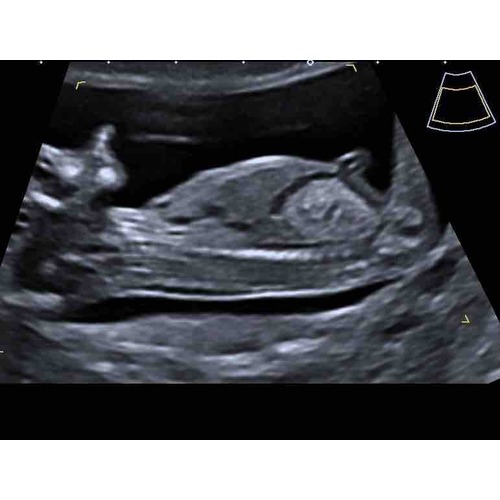

Hier ben ik 11+4, ik weet dat het iets te vroeg is, maar is er al iets te zien?

Hier ben ik 11+6, denk net iets te vroeg om het te kunnen zien. Wellicht dat iemand wel al wat kan zien. Ben zo benieuwd ☺️

Hoi hoi! Ben super benieuwd wat jullie denken. Echo 13+3 💖💙?

Hoi nubster🙂 ik heb nog 2 andere echo foto’s. Misschien zijn deze iets duidelijker? Baby’tje ligt wel ietsjes naar z’n linkerzijde

En de 2e foto

Kan iemand hier al iets uithalen? Jongen💙 meisje💗 Bij sommige Kan ik wel iets zien op de foto maar bij mij kan ik er niks uithalen 😊

Ik denk dat mijn post wat verloren is gegaan op einde van het vorige deel. Zou je willen kijken aub? Ben zo benieuwd... 🙈

Hier nog wat foto’s🙂